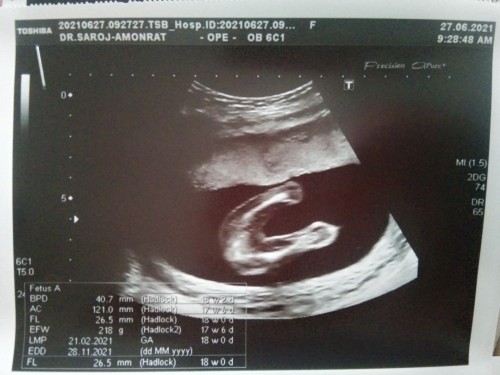

หมอบอกน่าจะเป็นผู้หญิง แต่แม่มั่นใจมาตลอดว่าลูกชายแน่นอน5555

หมอก็บอกว่าน่าจะเป็นผู้หญิง. แต่แม่อยากได้ลูกชายมากหวังมาตลอด5555

แม่หวังไว้มากและมั่นใจมากว่าลูกชายแน่นอน. แต่หมอบอกน่าจะเป็นผู้หญิง😅

หมอก็บอกค่ะน่าจะเป็นผู้หญิง. แต่แม่อยากมั่นใจ